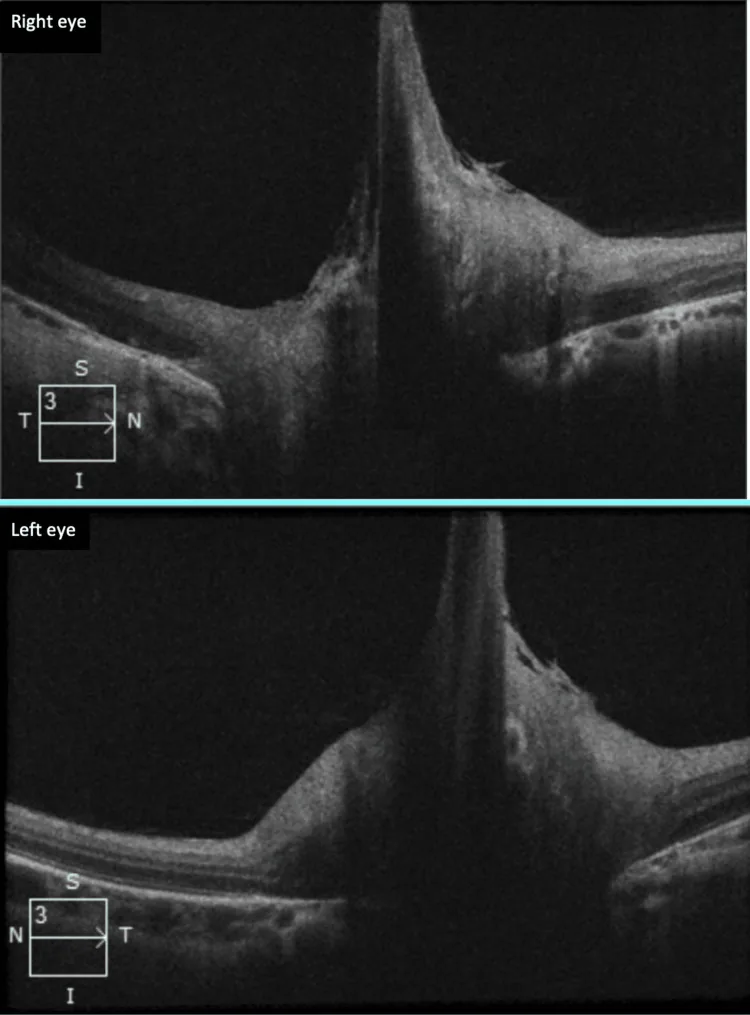

ベルグマイスター乳頭の診断は、眼底検査を基本とし、必要に応じてOCTや蛍光眼底造影(FA)を組み合わせる。

| OCT | 詳細な構造描出 | 確定診断に有用 |